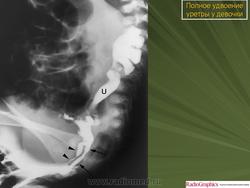

5. Удвоение уретры.